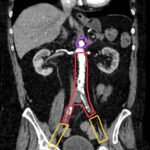

Aortoiliac occlusive disease (AOD) is a manifestation of peripheral arterial disease characterized by stenosis or occlusion of the distal aorta and iliac vessels. Advanced disease may present with symptoms of claudication to the buttock and thighs, erectile dysfunction, and absent or diminished femoral pulses bilaterally. Here, we discuss a case of a 71-year-old male who presented with acute bilateral lower extremity pain and weakness. Pulses were undetectable bilaterally at the groin prompting emergent imaging and vascular surgery consultation due to the suspected diagnosis of AOD. The patient was taken for bilateral femoral artery cut downs with embolectomy. The patient made an impressive recovery with preservation of motor function of lower extremities. In this case report we discuss pertinent workup and management of a patient suspected to be suffering from AOD.